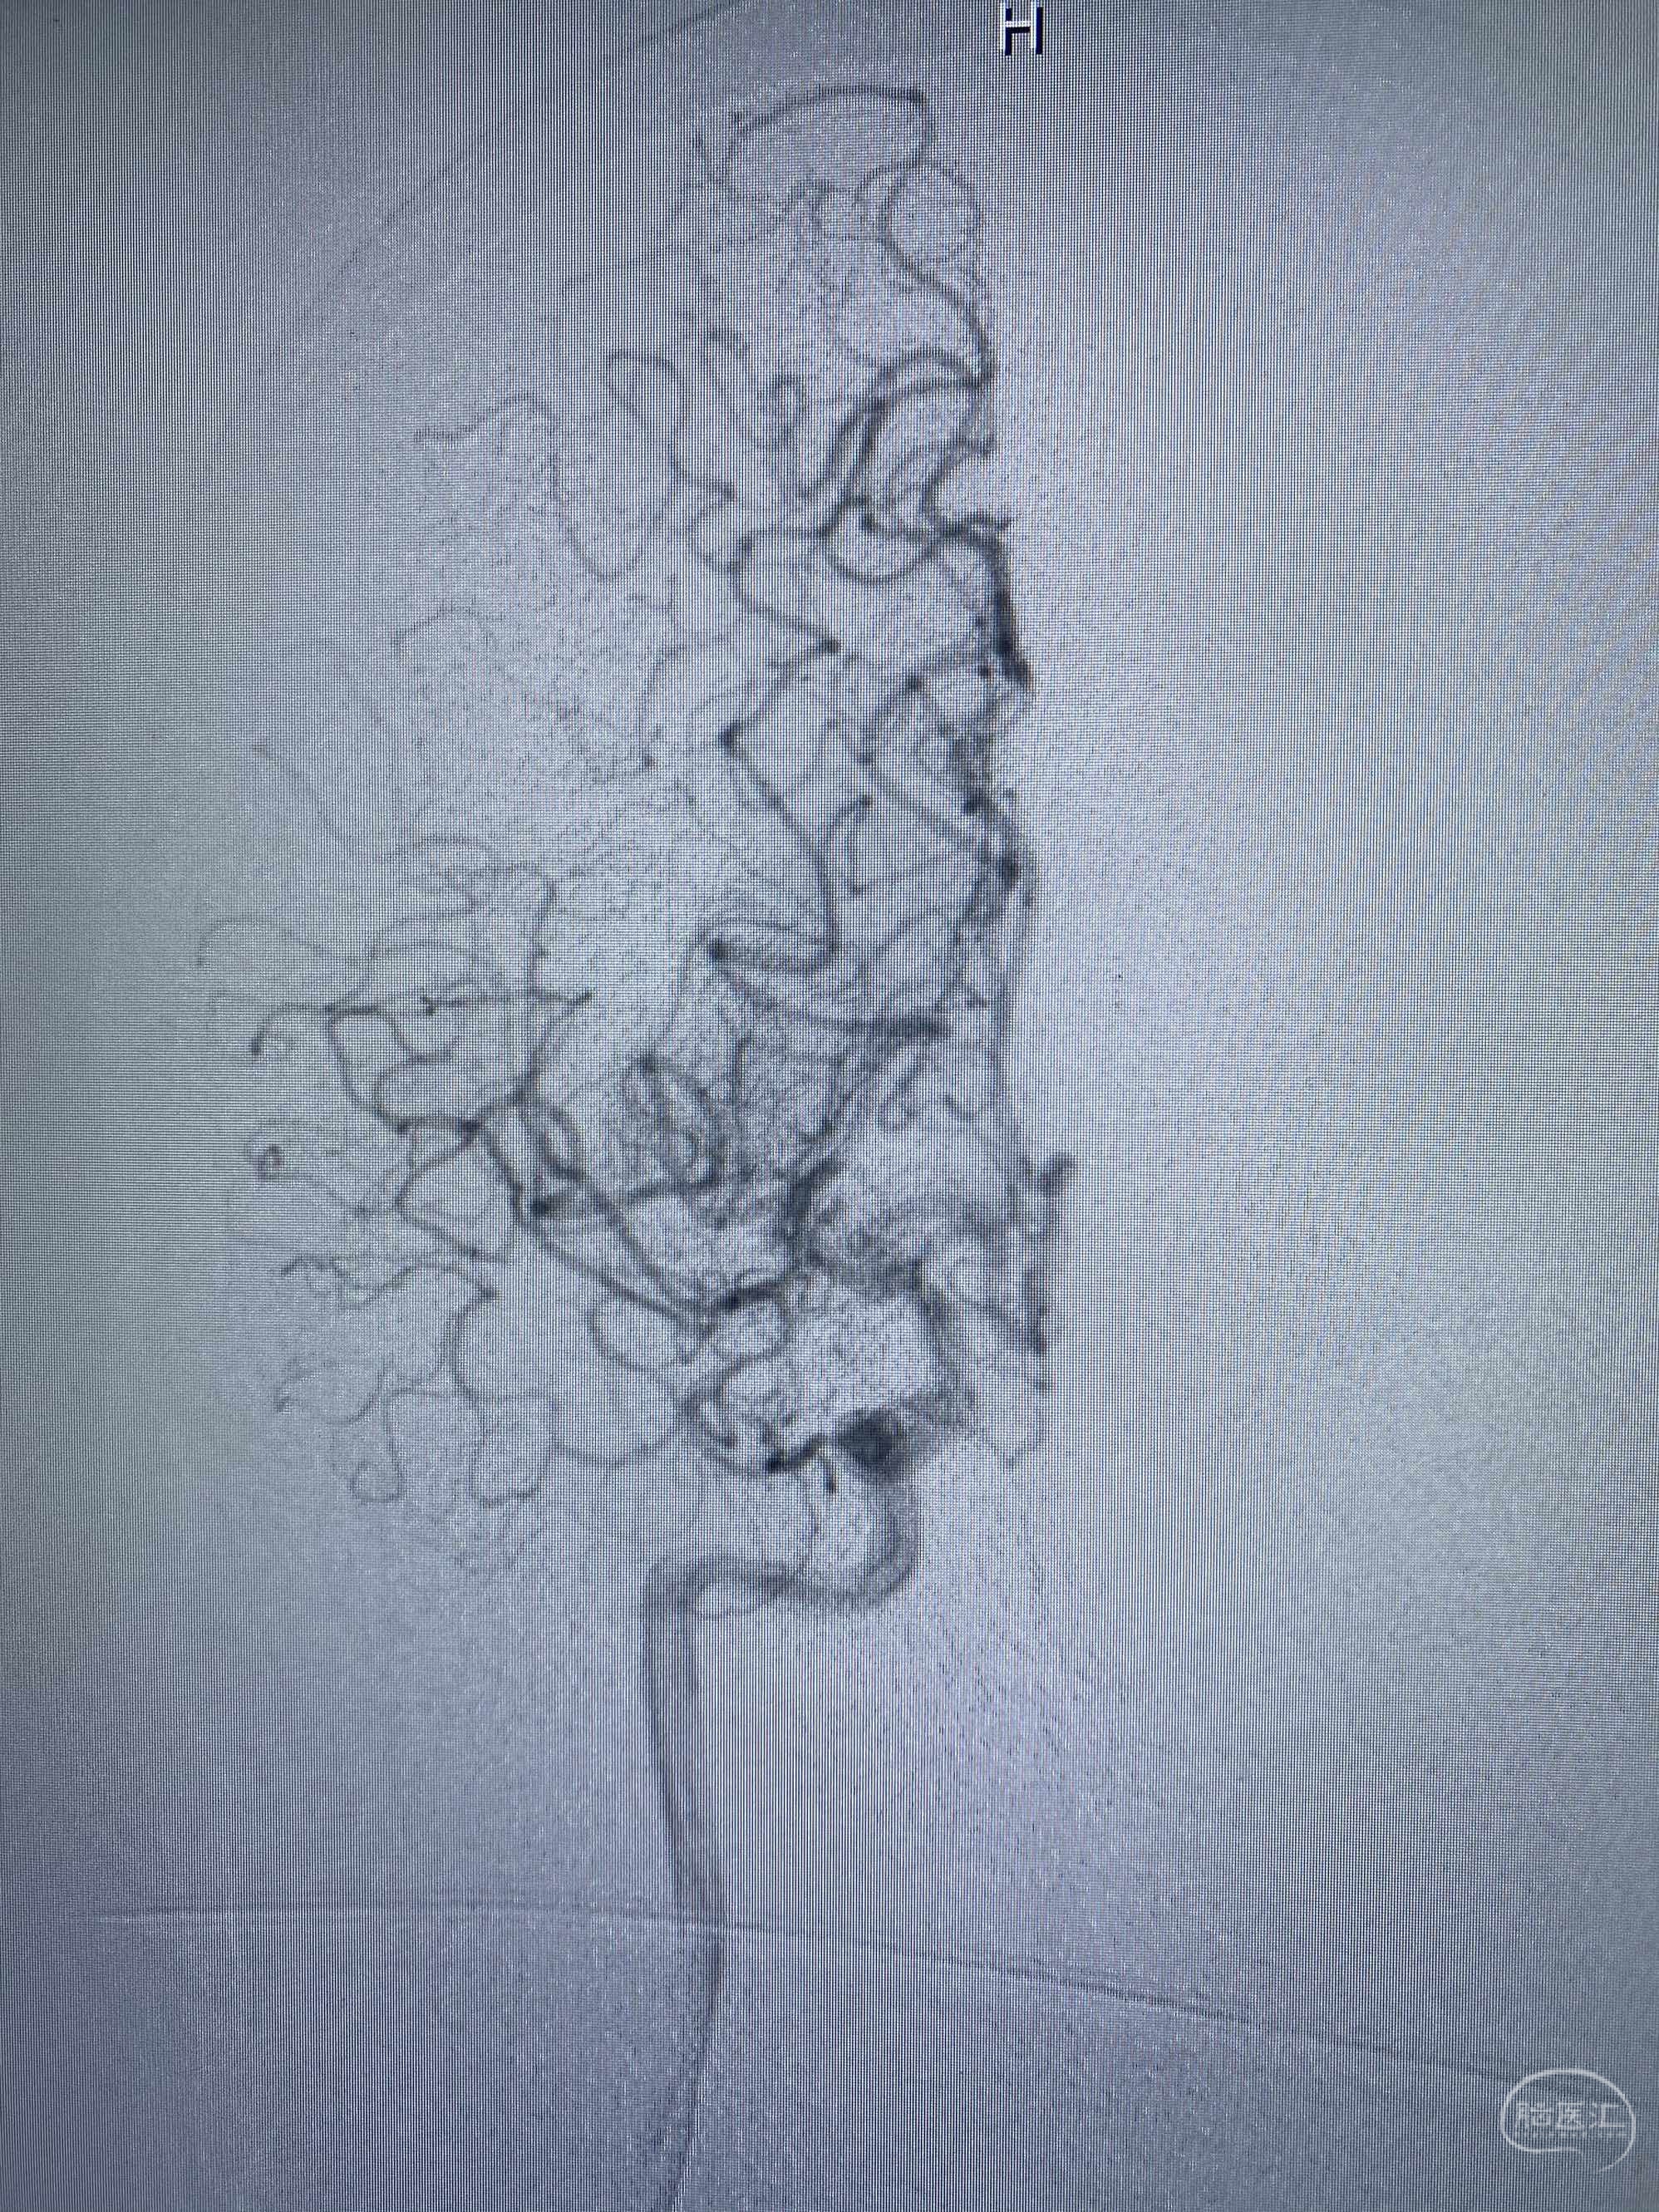

MLS,M79Y,sah,双侧MCA烟雾病,Heubner返动脉瘤,前交通段开窗,细支发出Heubner返动脉,瘤颈细长,瘤颈口比微导管细,弹簧圈2mmx3cm“隔山打牛”填塞治愈,Heubner返动脉保留。

Heubner返动脉是由大脑前动脉A1末端发出的豆纹动脉,由于走形和A1段相反,故称Heubner返动脉,该动脉梗塞可能引起尾状核头梗塞,引起偏瘫和面瘫,便身震颤等症状。